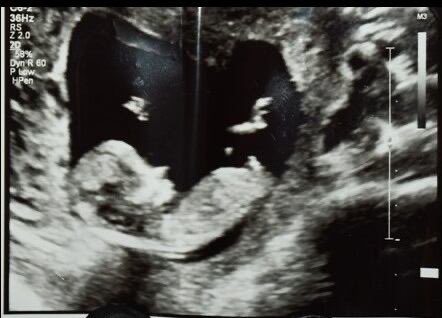

Según la fiscalía, Donovan Faison, de 23 años, reaccionó violentamente cuando Kaylin Fiengo le envió por mensaje de texto una foto de dos https://t.co/Qt0HdfPAQE